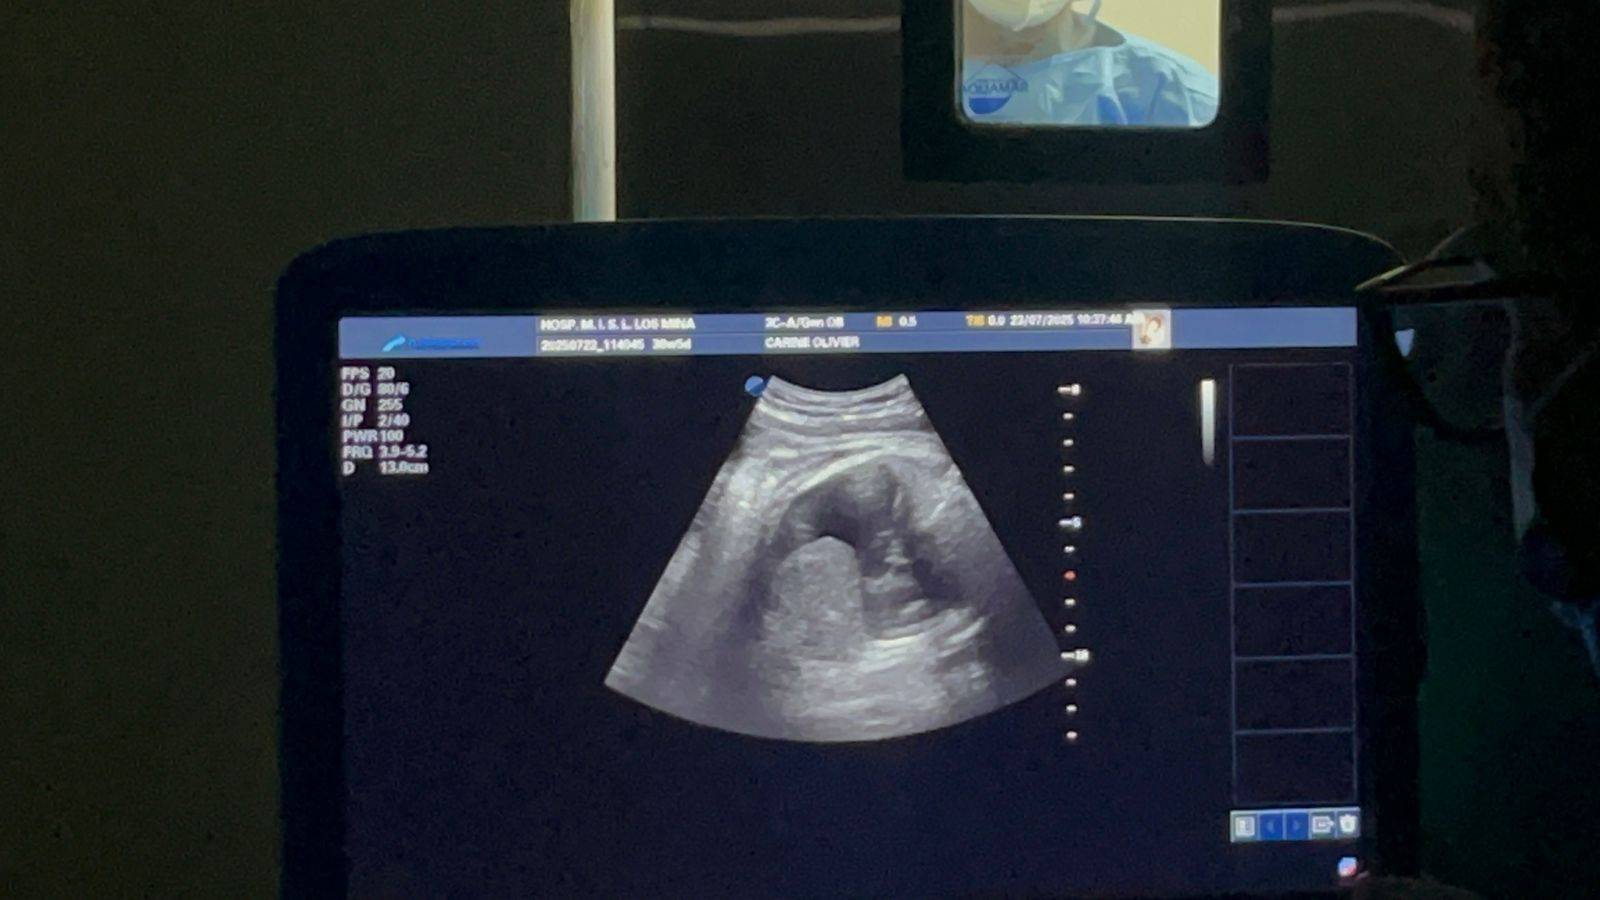

El director del Materno Infantil de Los Mina explicó que se logró en una primera etapa prenatal, coordinado por los doctores Ramiro Díaz y Virginia Pérez, al realizar un drenaje toracoamniótico, el cual consiste en extraer líquido del espacio pleural y pericárdico que tras el nacimiento impediría que el bebé respirara de manera adecuada.